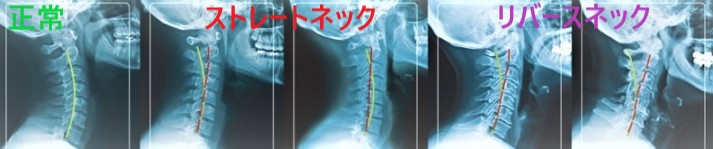

ストレートネックは、レントゲンを見ないときちんと判断できません

ストレートネックといっても、人それぞれ微妙に違います。

当院では、レントゲンによる正確な分析を行い、まずあなたのストレートネックをきちんと知ることができます。